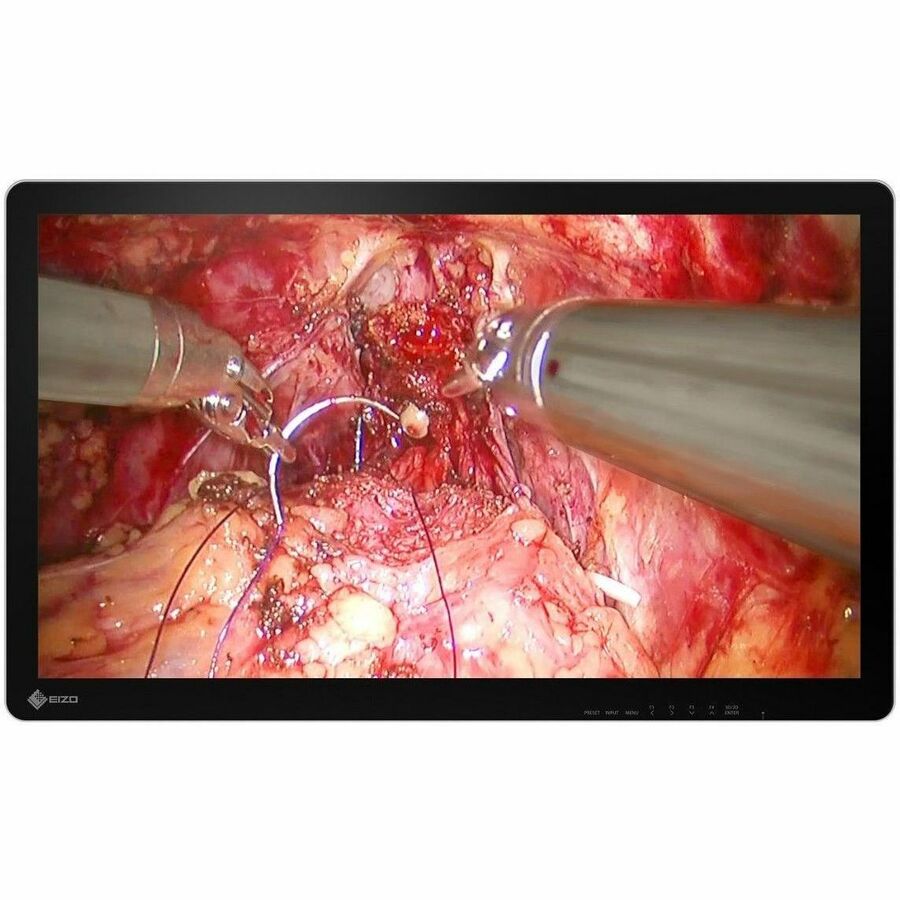

A 32-inch widescreen 3D surgical monitor with 4K UHD (3840 x 2160 pixels) for faithful reproducing stereoscopic images for endoscopy, microsurgery, and other high-precision procedures.

During procedures, the operating surgeon needs to be able to differentiate between varying color tones. The monitor supports the BT.2020 4K video color standard to ensure that subtle differences between shades of reds and yellows captured by BT.2020-supported cameras are distinguishable on the screen.

This monitor faithfully reproduces stereoscopic images in 4K UHD resolution (3840 x 2160) at a high brightness of up to 850 cd/m², achieving both detail and depth for endoscopy and microsurgery.